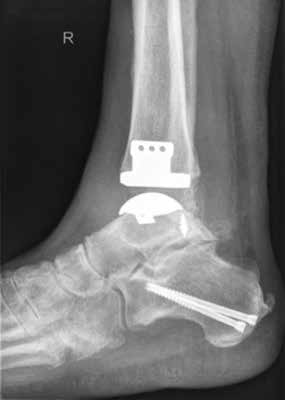

Endoprothetik des OSG

Die Indikation zur endoprothetischen Versorgung einer OSG-Arthrose ist gründlich zu stellen. Darunter fällt die schwere Arthrose jeglicher Ätiologie mit täglich intensiven Schmerzen, hochgradigem Gelenkfunktionsverlust und Gelenkdestruktion. Voraussetzungen sind eine gute Knochenqualität sowie mittleres Alter ohne schwere systemische Vorerkrankungen. Auch bei der Implantation von Endoprothesen des oberen Sprunggelenkes ist es wichtig, bestehende Achsfehlstellungen entweder in gleicher Sitzung oder zuvor zu korrigieren. Sofern nach Achskorrektur die Versorgung mittels einer Endoprothese noch notwendig ist, soll damit die Funktionsfähigkeit des Gelenks, eine Schmerzeliminierung und eine Verbesserung der Lebensqualität erreicht werden (Abb. 6). Kontraindikationen sind neben den bereits oben genannten: bestehende Osteonekrosen, periphere arterielle Verschlusskrankheit, periphere Neuropathie, bestehende oder stattgehabte Gelenkinfektion und schwere Bandinstabilität 56.

Im Vergleich zur Endoprothetik des Hüft- und Kniegelenks bestehen höhere Komplikationsraten bei der Endoprothese des Sprunggelenks. Intraoperativ sind dies meist operationstechnische Komplikationen bei der Osteotomie der Malleoli, beim Sägen oder beim Positionieren der Prothesenkomponenten 57. Postoperativ sind dies vornehmlich Wunddehiszenzen und Infektionen 58, während im Langzeitergebnis aseptische Prothesenlockerung, periprothetische Stressfrakturen und Retraktion der Gelenkkapsel sowie der periartikulären Weichteile auftreten 59.